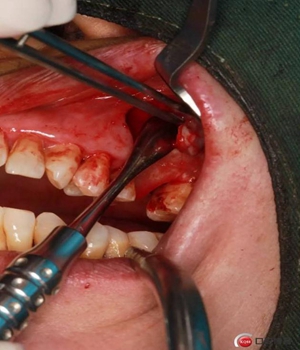

改良式外提升工具盒-外提 科貿(mào)嘉友收錄

大家好,我是梁老師的助理小依。由于梁老師每天手術(shù)檔期安排較滿,加上經(jīng)常出差講課,沒有時(shí)間整理病例 。為了方便大家更及時(shí)的了解梁老師最新手術(shù)動(dòng)態(tài),以后將由我為大家整理并推送梁老師最新經(jīng)典案例。案例文字旁白少,但圖片會(huì)盡量完整展示手術(shù)全過程,供大家學(xué)習(xí)參考。有任何問題,可以留言,梁老師會(huì)親自為大家解答。感謝大家對梁老師的支持和關(guān)注!